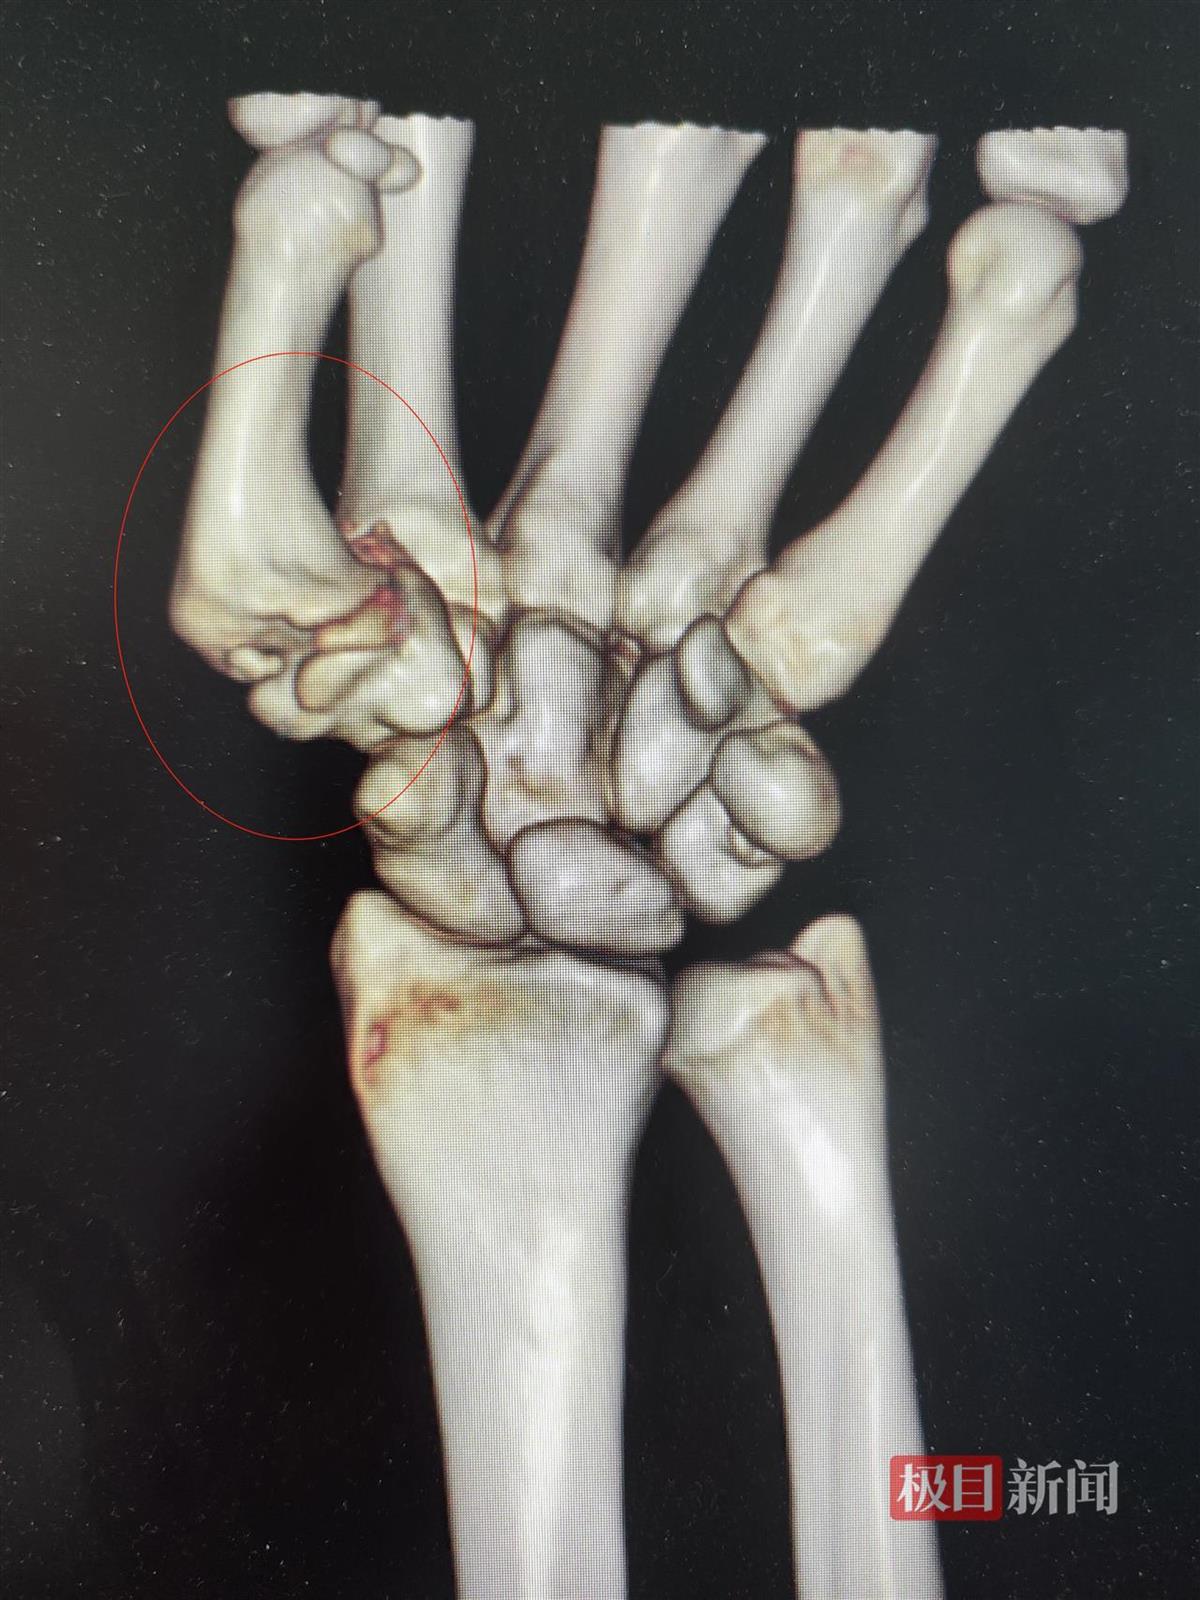

手术前刘女士手部影像图

在该院骨科门诊,医生接诊后详细询问刘女士病史,并为其进行了相关检查。发现刘女士左手第一腕掌关节间隙几乎完全消失,形成大量骨赘,诊断为第一腕掌骨关节炎。